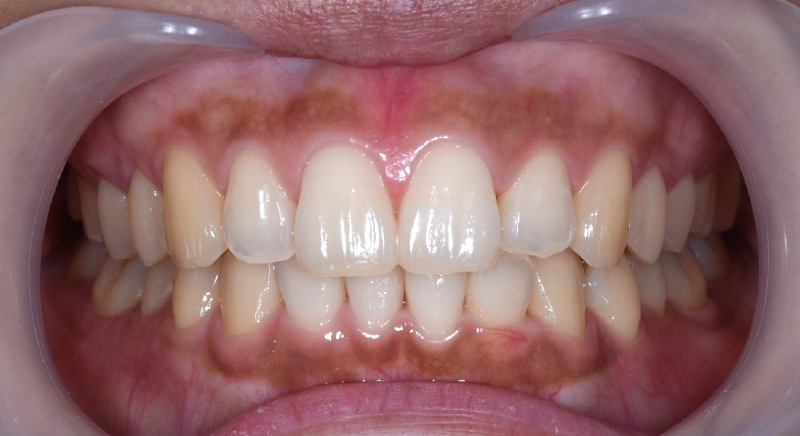

| 主訴 | 前歯で噛めない、 奥歯だけで食事するのが困っている |

|---|---|

| 治療期間 | 3年3か月 |

| 治療費 | ¥980,000(税込) |

| 治療内容 | 目立ちにくいマウスピース矯正(非抜歯矯正) 歯と歯の間に隙間をつくることにより、 歯列弓を広げながら治療を行いました。 |

| 治療のリスク | ・後戻りする可能性があるので リテーナーを最低でも矯正期間以上はつけること ・歯の移動中に、歯の神経が過敏になり冷たいものや熱いものがしみたりする場合があります。 |